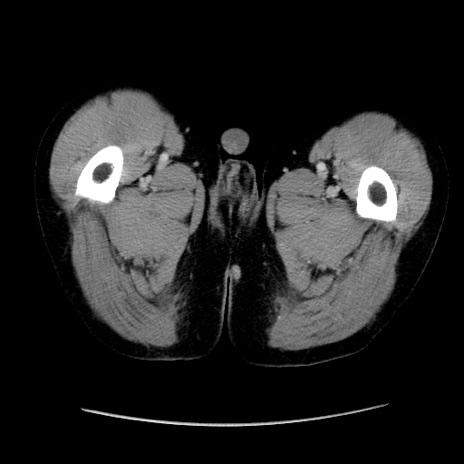

症例37(横断像)

【症例】40歳代 男性

【主訴】腹痛

【現病歴】4時間ほど前に電車に乗車中に臍部上より腹痛出現。徐々に増悪し起立困難となり、救急外来受診。生ものは数日食べていない。今朝お雑煮を食べた。

【身体所見】BT 36.8℃、BP 117/84mmHg、HR 91/min、SpO2 97%、苦悶様、腹部:臍上部広範囲圧痛あり、反跳痛±

【データ】WBC 8100、CRP 0.03